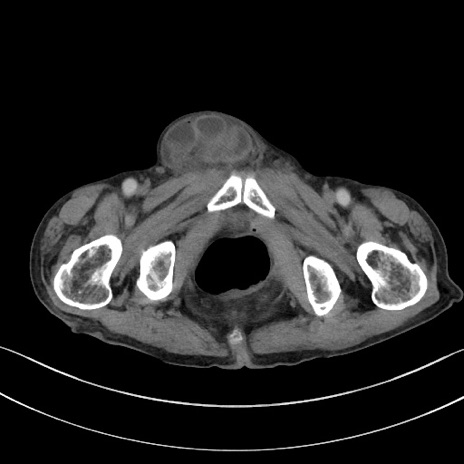

【症例】 70歳代男性

【主訴】右鼠径部腫瘤、疼痛

【現病歴】本日朝より上記主訴あり、受診。

【既往歴】膀胱癌にて膀胱全摘、両側尿管皮膚瘻

【データ】WBC 5600、CRP 0.56